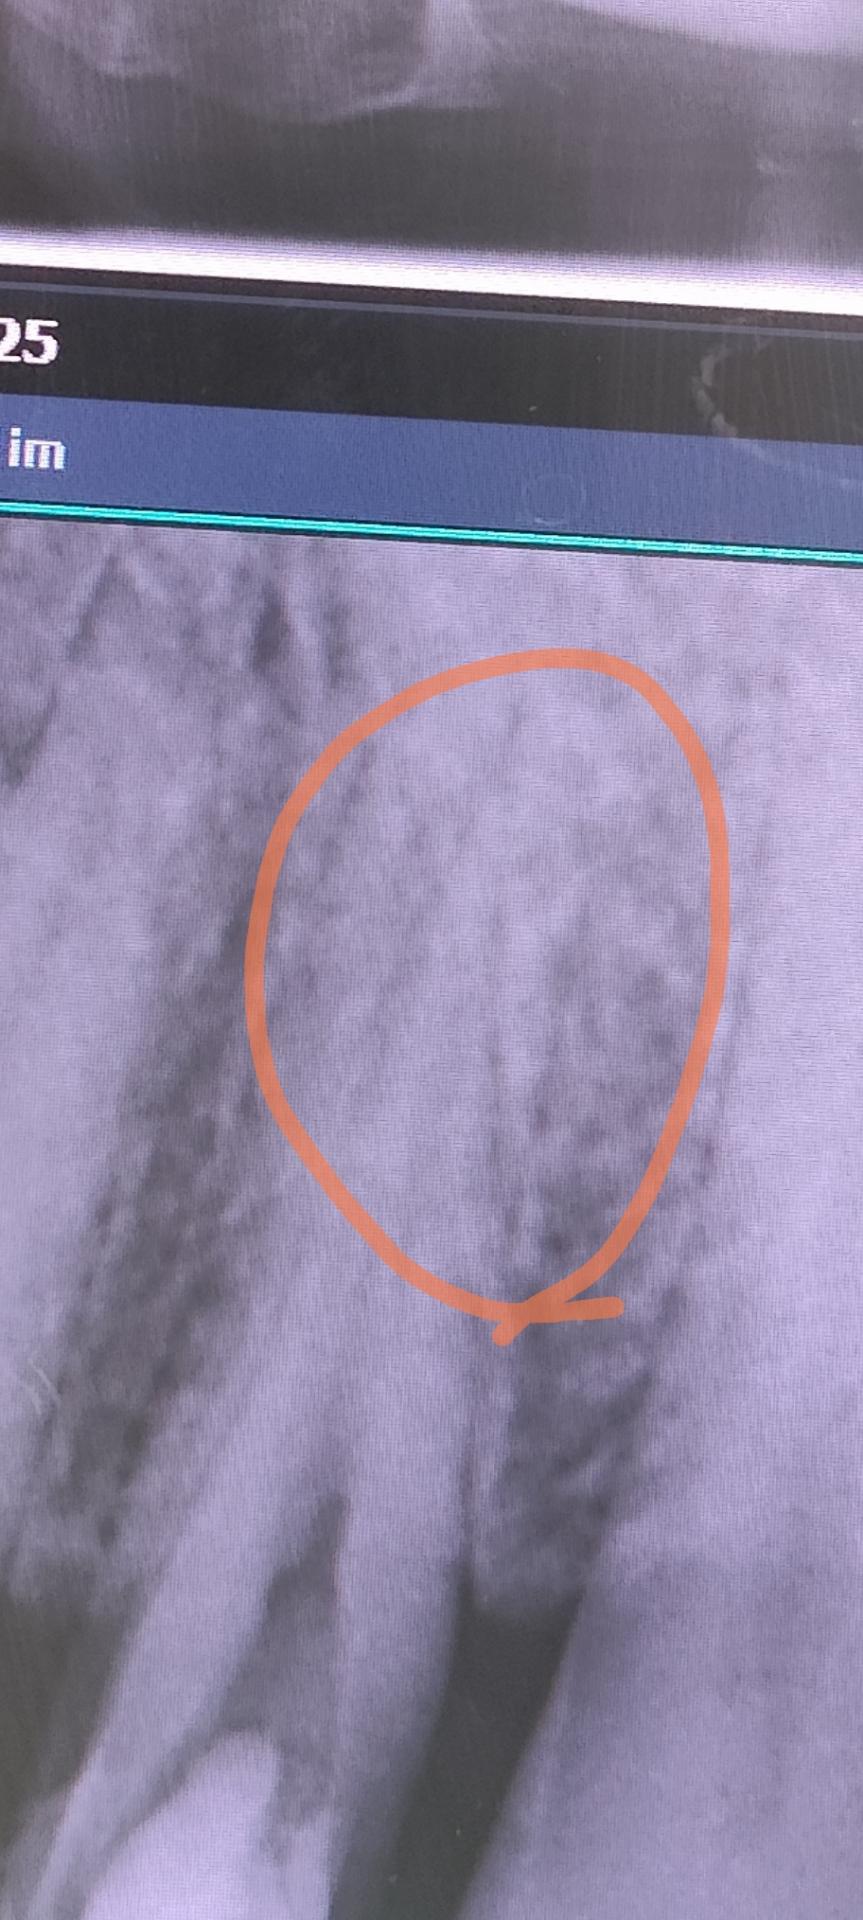

치아 뿌리 파절인지 엑스레이사진 한번봐주심 감사합니다.

액스레이 사진상 동구라미친 부위 사선으로 금이 가있는듯이 보이는데

치아 뿌리 파절인지 한번 봐주시면 감사합니다.

사진으로는 치아 뿌리에 파절이 되었는지 정확한 확인이 어려워 보입니다. 치아에 이상이 없음에도 불구하고 불편감이 있다면 해당 부위에 너무 과도한 힘이 가해졌을 수 있습니다. 이런 경우 치아에 가해지는 힘을 줄인다면 불편감을 줄일 수도 있습니다.

1. 엑스레이상에서 보이기로는 치근 파절보다는 앞,뒤로 뿌리 2개가 겹쳐보이면서 약간 어지지한 것 같습니다

2. 각도를 틀어서 한번 더 엑스레이를 찍어보면 좋을 것 같습니다

3. 특히 씹을때 찌릿하게 아픈거라면 치근파절이 맞을 수도 있습니다